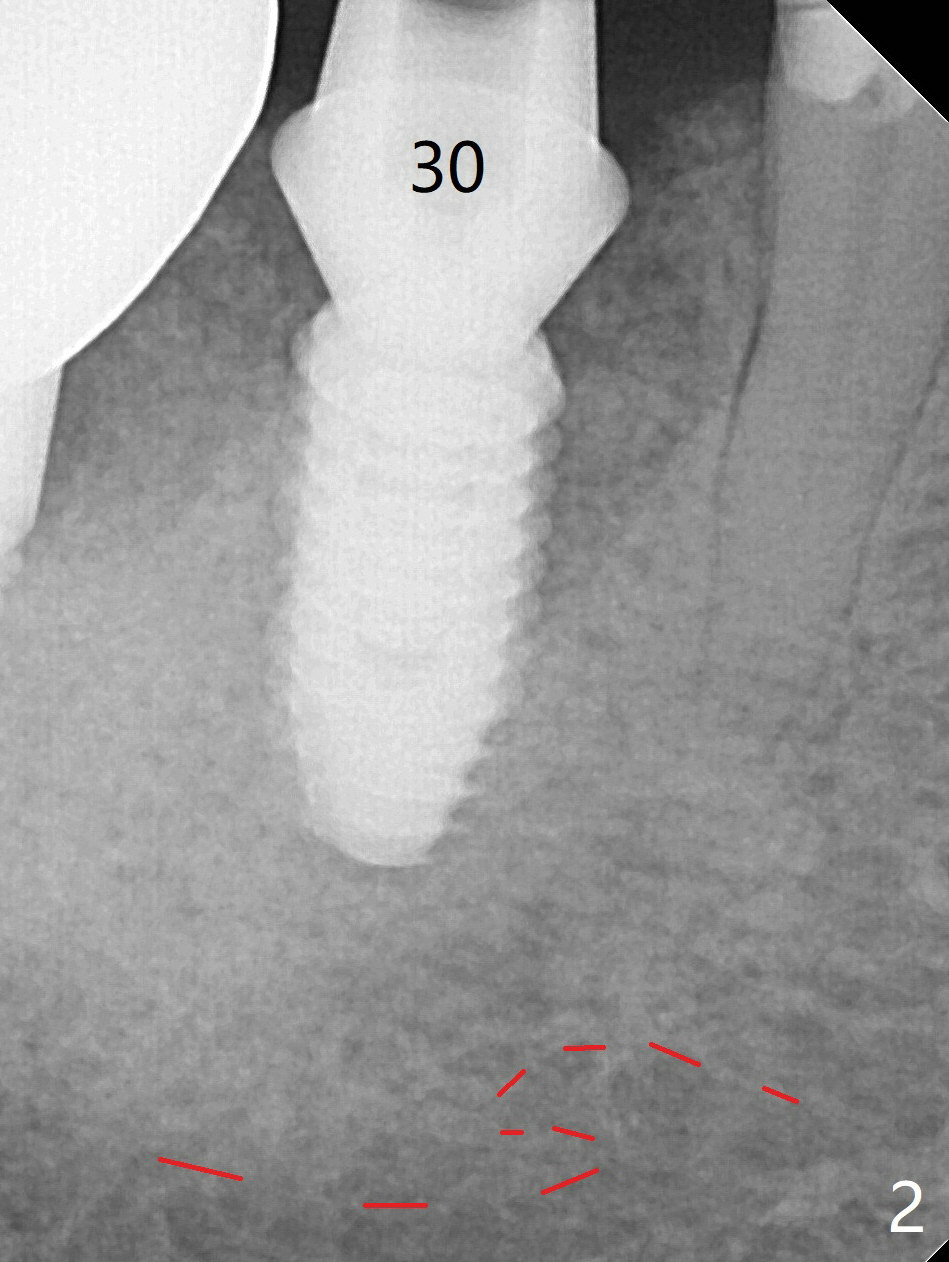

Trajectory is as good as expected with >50 Ncm (Fig.2 (red dashed line: superior border of the Inferior Alveolar Canal)). With insertion of Vanilla allograft with autogenous bone and a 6.5x4(3) mm cementation abutment, an immediate provisional is fabricated to keep the graft in place. While the crestal bone resorbs (Fig.4 *), the density of the mesial socket increases 6.5 months postop.